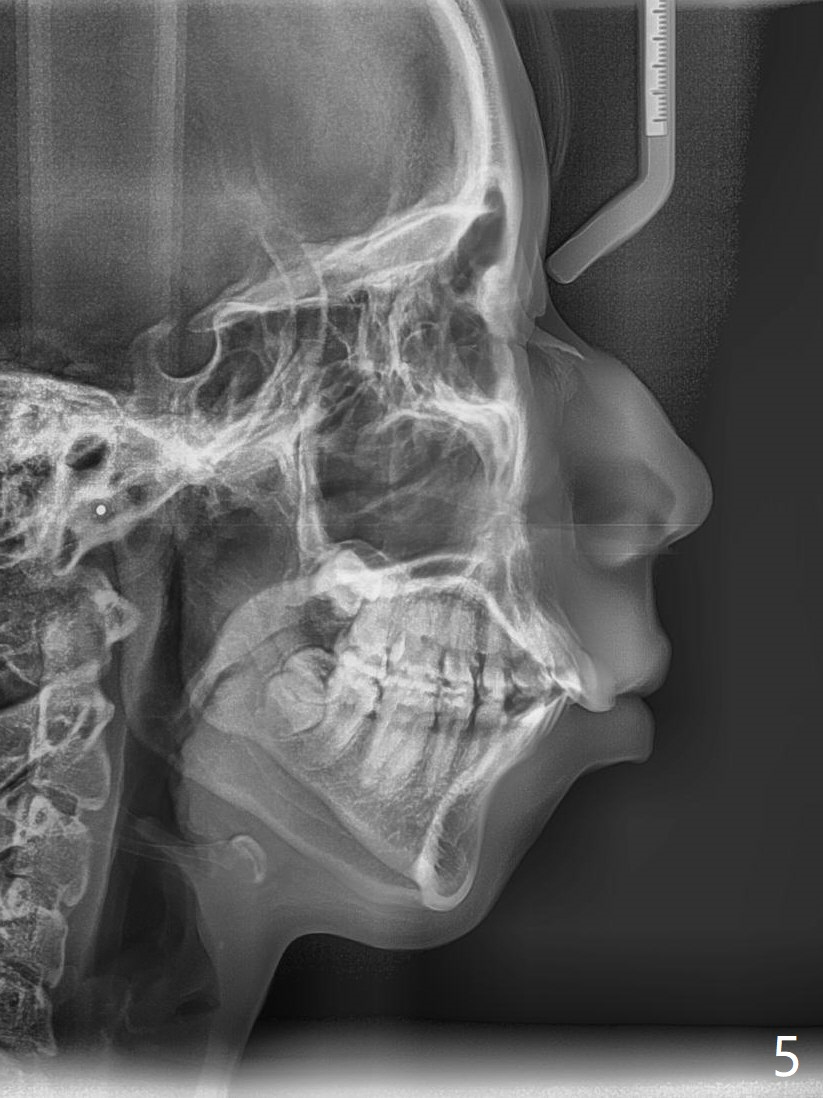

A 15-year-old woman has protrusive lips and retrusive chin (Fig.1-6). Canines and molars have Class I occlusion (Fig.7-9). With 4 bi extraction and 5-7 anchorage (Fig.10-12), 3s will be distalized after 16x16 wires, followed by posted wire retraction of 4 incisors.